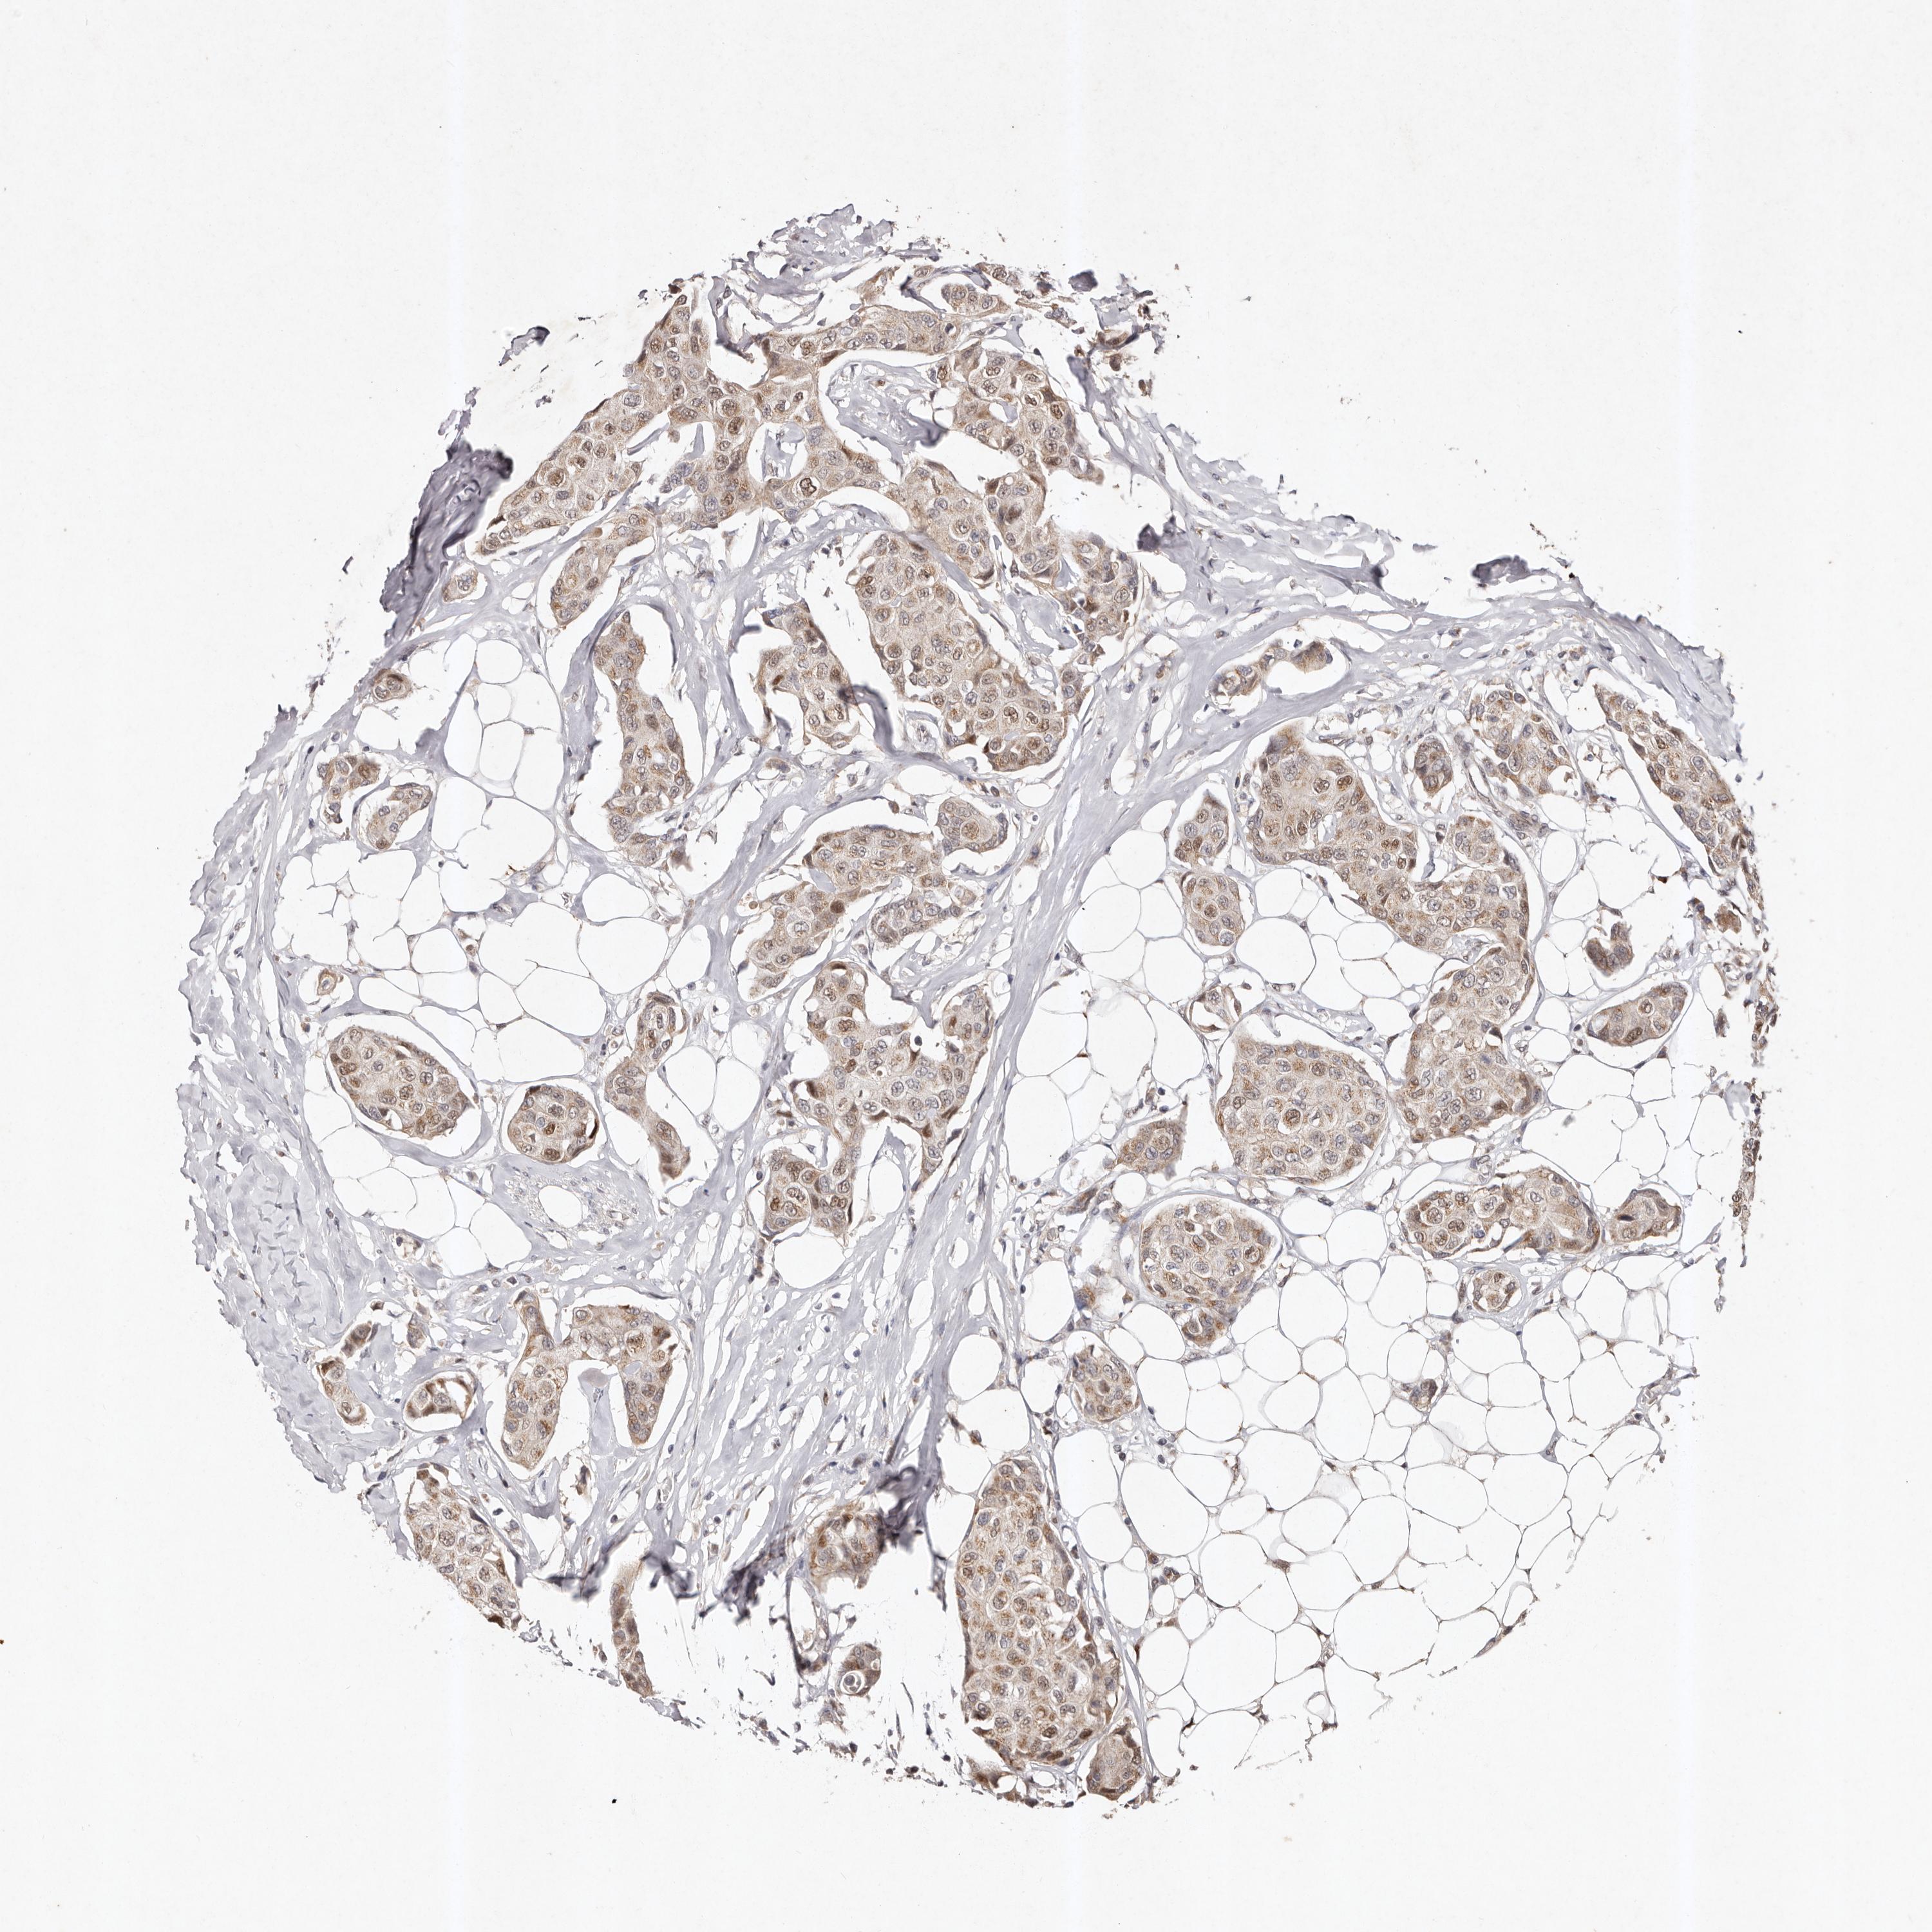

CANCER BREAST CANCER Show tissue menu

BRCA TCGA BRCA VALIDATION PROTEIN EXPRESSION